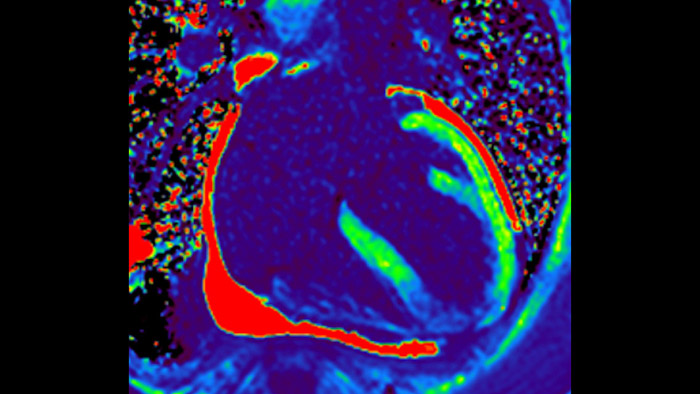

IntelliSpace Portal MR Caas5,6 Strain7 assists in patient diagnosis and monitoring by providing global strain parameters such as global longitudinal strain (GLS), global circumferential strain (GCS), and global radial strain (GRS), using short and long axis MR images, as well as describing the myocardium deformation- such as shortening, thickening, and lengthening during the cardiac cycle.

Today's diagnostics often cannot detect heart dysfunction until symptoms occur. MyoStrain utilises segmental strain to measure 48 segments of the heart and provides physicians with a unique diagnostic tool to help identify regional dysfunction before the heart as a whole is affected.